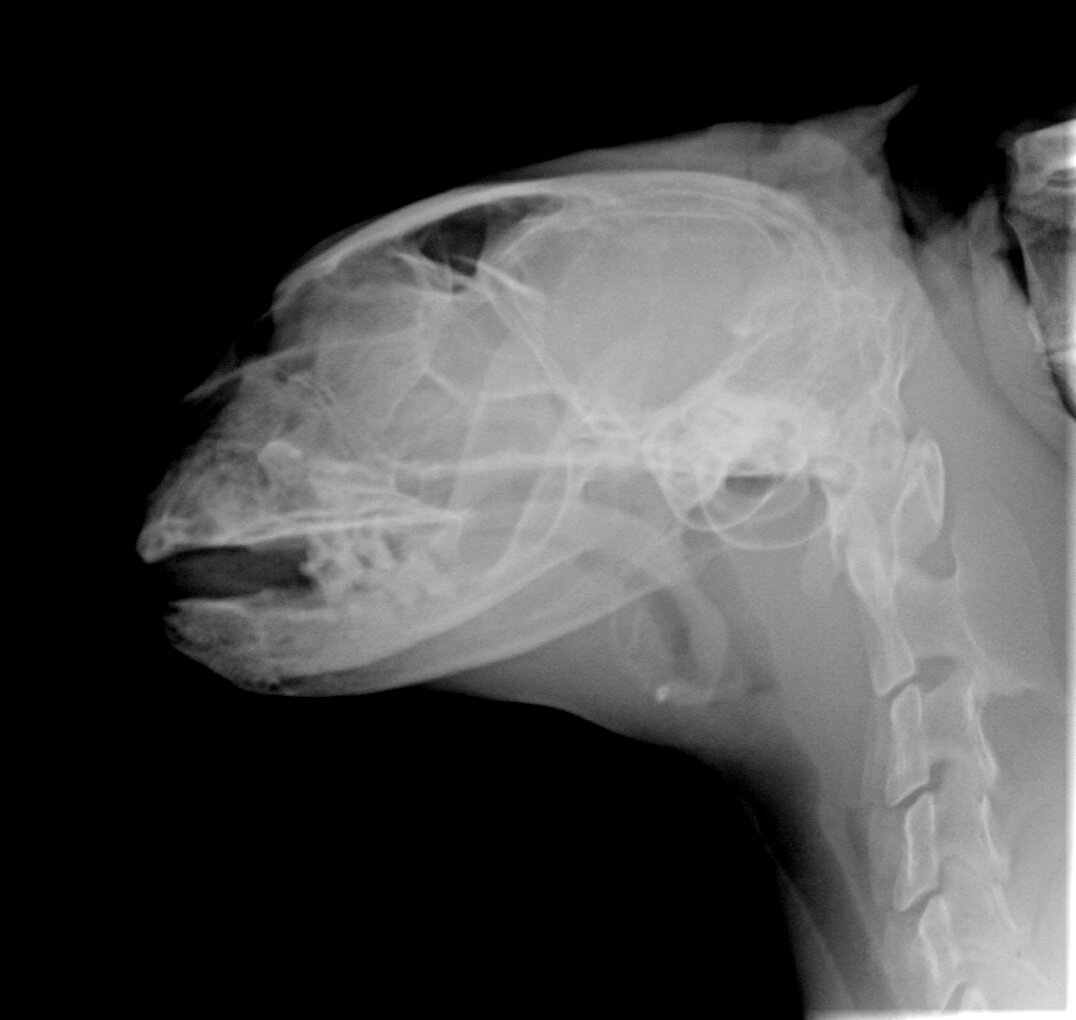

Персику снова сделали рентген, назначили лечение и боится волонтёр, что это ещё не конец. Зубы пока хорошие, их удалять врач отказался, а вот в лунках идёт воспалительный процесс из-за которого котик не может кушать.